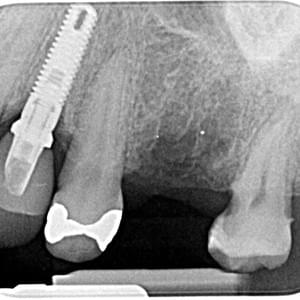

Radiografías

Periapicales, bitewing oclusales

Equipo intraoral

Sirona Heliodent Plus

Colimación rectangular que disminuye en 92% la dosis necesaria, cumpliendo las mas estrictas normas europeas.